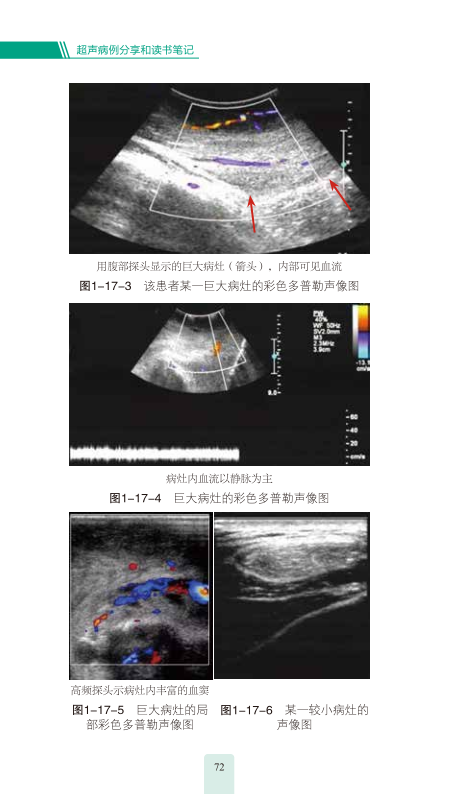

本书汇集了作者多年的宝贵的临床经验,综述了近年来超声领域的新理论、新观点、新进展,有助于读者系统了解相关知识和进展;通过介绍病例的方式展示超声相关知识,深入剖析超声诊断思维过程,系统总结超声相关问题,将生动的病例和缜密的思维、规范的诊断程序、新的指南和循证研究结果有机结合起来,有助开阔思路。